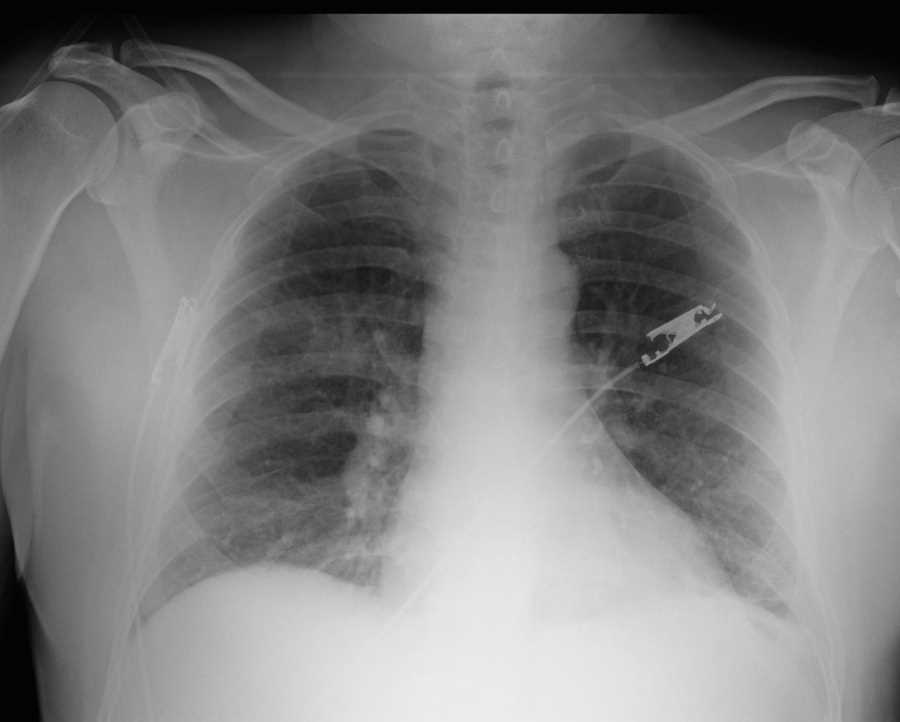

Abdominal x-ray in patient with severe of abdominal pain. There is marked distention of the colon. The sigmoid colon is twisted with a coffee bean appearance. This is a characteristic x-ray finding of sigmoid volvulus.